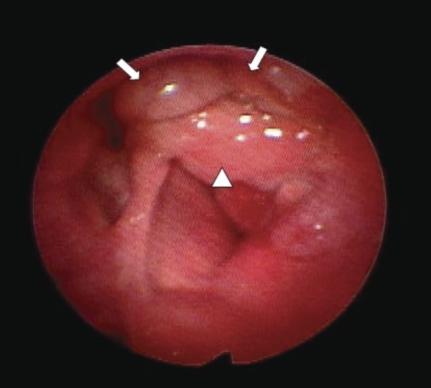

声门上区原发性黏液样脂肪肉瘤

Primary myxoid liposarcoma of the supraglottic larynx.

Sarcomas are a rare occurrence accounting for roughly 1% of all cancer cases reported. Of these, 9-18% will be identified as liposarcoma. Overall, only 4-9% of all liposarcomas occur in the head and neck region. As such, it is a rare event to see a primary liposarcoma of the aerodigestive tract. These tumors are typically misdiagnosed secondary to their indolent, asymptomatic course and similarities in appearance to other benign lesions. An understanding of these lesions will help clinicians appropriately manage their patients. We present a case of a 60-year male with a primary supraglottic myxoid liposarcoma, and provide relevant information about liposarcomas.

摘要

肉瘤较为罕见,约占所有报告癌症病例的1%。其中,9% - 18%将被确诊为脂肪肉瘤。总体而言,所有脂肪肉瘤中仅有4% - 9%发生于头颈部区域。因此,发生于气消化道的原发性脂肪肉瘤实属罕见。这些肿瘤通常因生长缓慢、无症状以及外观与其他良性病变相似而被误诊。了解这些病变将有助于临床医生对患者进行恰当的治疗。我们报告一例60岁男性原发性声门上黏液样脂肪肉瘤病例,并提供有关脂肪肉瘤的相关信息。